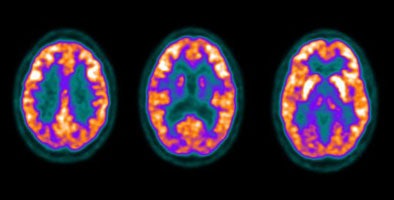

Normal brain activity: The image below demonstrates normal FDG brain activity. |

|

|